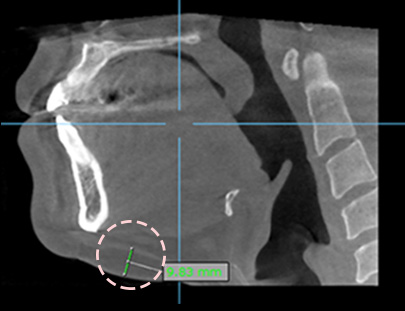

3D-CT 촬영 후

상담을 진행하여

지방 부위를 보다

명확하게 체크

· 지방량, 근육 위치, 피부 탄력을 고려한 라인 교정

에이탑성형외과 얼굴지방흡입은 단순히 만져지는 느낌에 따라 빼는 지방흡입이 아니라 3D CT롤 확인하고 근육 안쪽가지 제대로 빼는 수술입니다. 에이탑은 얼굴지방흡입의 다양한 노하우를 보유하고 있어 높은 기술력으로 근육층 안에 있는 지방까지 제거하여 흡입의 효과를 더욱 또렷하게 하며 오래 유지될 수 있도록 합니다.